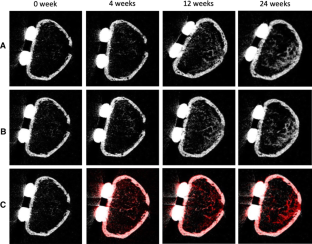

A total of 10 fracture sites identified from four patients with a distal radius fracture who underwent internal fixation with a volar locking plate (mean age 68.8 years, all women) were investigated. HR-pQCT was performed within a week (baseline) 4, 12, and 24 weeks after fracture. Rectangular region of interest (ROI) was established in the fracture site, inner callus, and external callus area, and the changes in bone mineral density (BMD) in each region were analyzed.

Results

From baseline to 24 weeks post-fracture, the BMD changed from 105.5 (95% CI 98.6–113) to 428.0 (331–554) mgHA/ccm at the fracture site, from 111.0 (104–119) to 375.3 (290–486) mgHA/ccm at the inner callus area, and from 98.5 (91.6–106) to 171.6 (132–222) mgHA/ccm at the external callus area. The BMD increased at the fracture site and inner callus area, but increased only slightly at the external callus area. At 24 weeks post-fracture, the BMD at the fracture site and inner callus area was significantly higher than the external callus area.

Fig. 3 3D